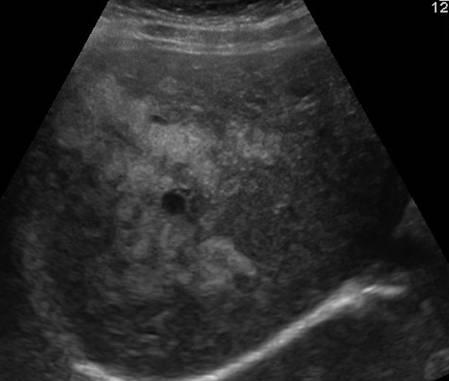

Gan nhiễm mỡ

» Thông tin: Nữ giới – 40 tuổi.

» Lâm sàng: Kiểm tra sức khỏe.